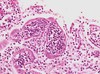

This type of glomerulonephritis shown below is illustrated by the compression and breaking of capillary loops (black stained) and the leaking of fibrotic material into the Bowman’s space:

crescentic glomerulonephritis; she stressed that crescentic GN always implies vasculitis.

what type of lesion is shown here?

crescentic GN